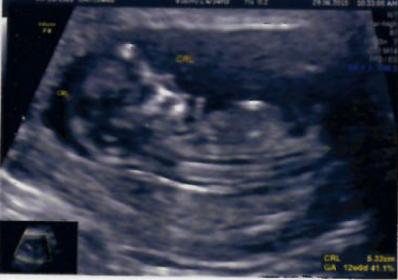

20 W imageAttachment 28071

I think girl as I can't see anything on this potty shot xxx

Maybe girl!

hi how do u predict? Bcos in first pic I could see a nub pointing upwards?? Could anyone clarify??